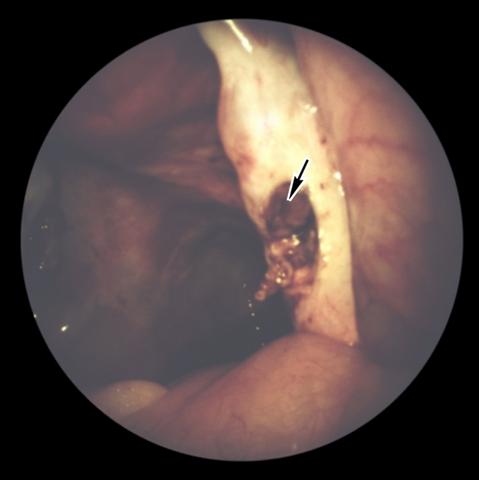

Рис. 3. Лапароскопическая картина поликистозного яичника после проведения биопсии: виден дефект ткани поликистозного яичника, образовавшийся в результате биопсии (указан стрелкой).